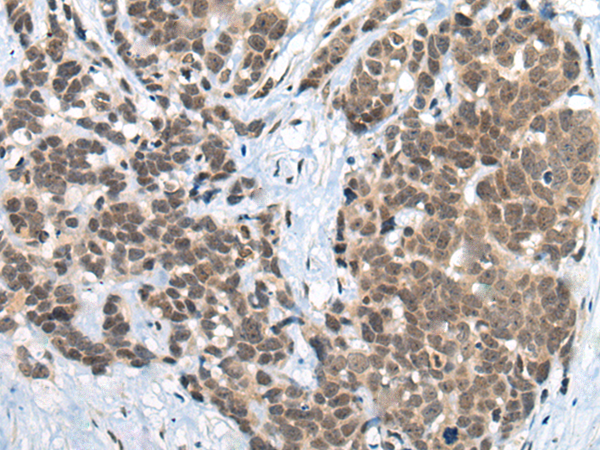

The image is immunohistochemistry of paraffin-embedded Human thyroid cancer tissue using (ZNF83 Antibody) at dilution 1/50.

The image is immunohistochemistry of paraffin-embedded Human colorectal cancer tissue using (ZNF83 Antibody) at dilution 1/50.